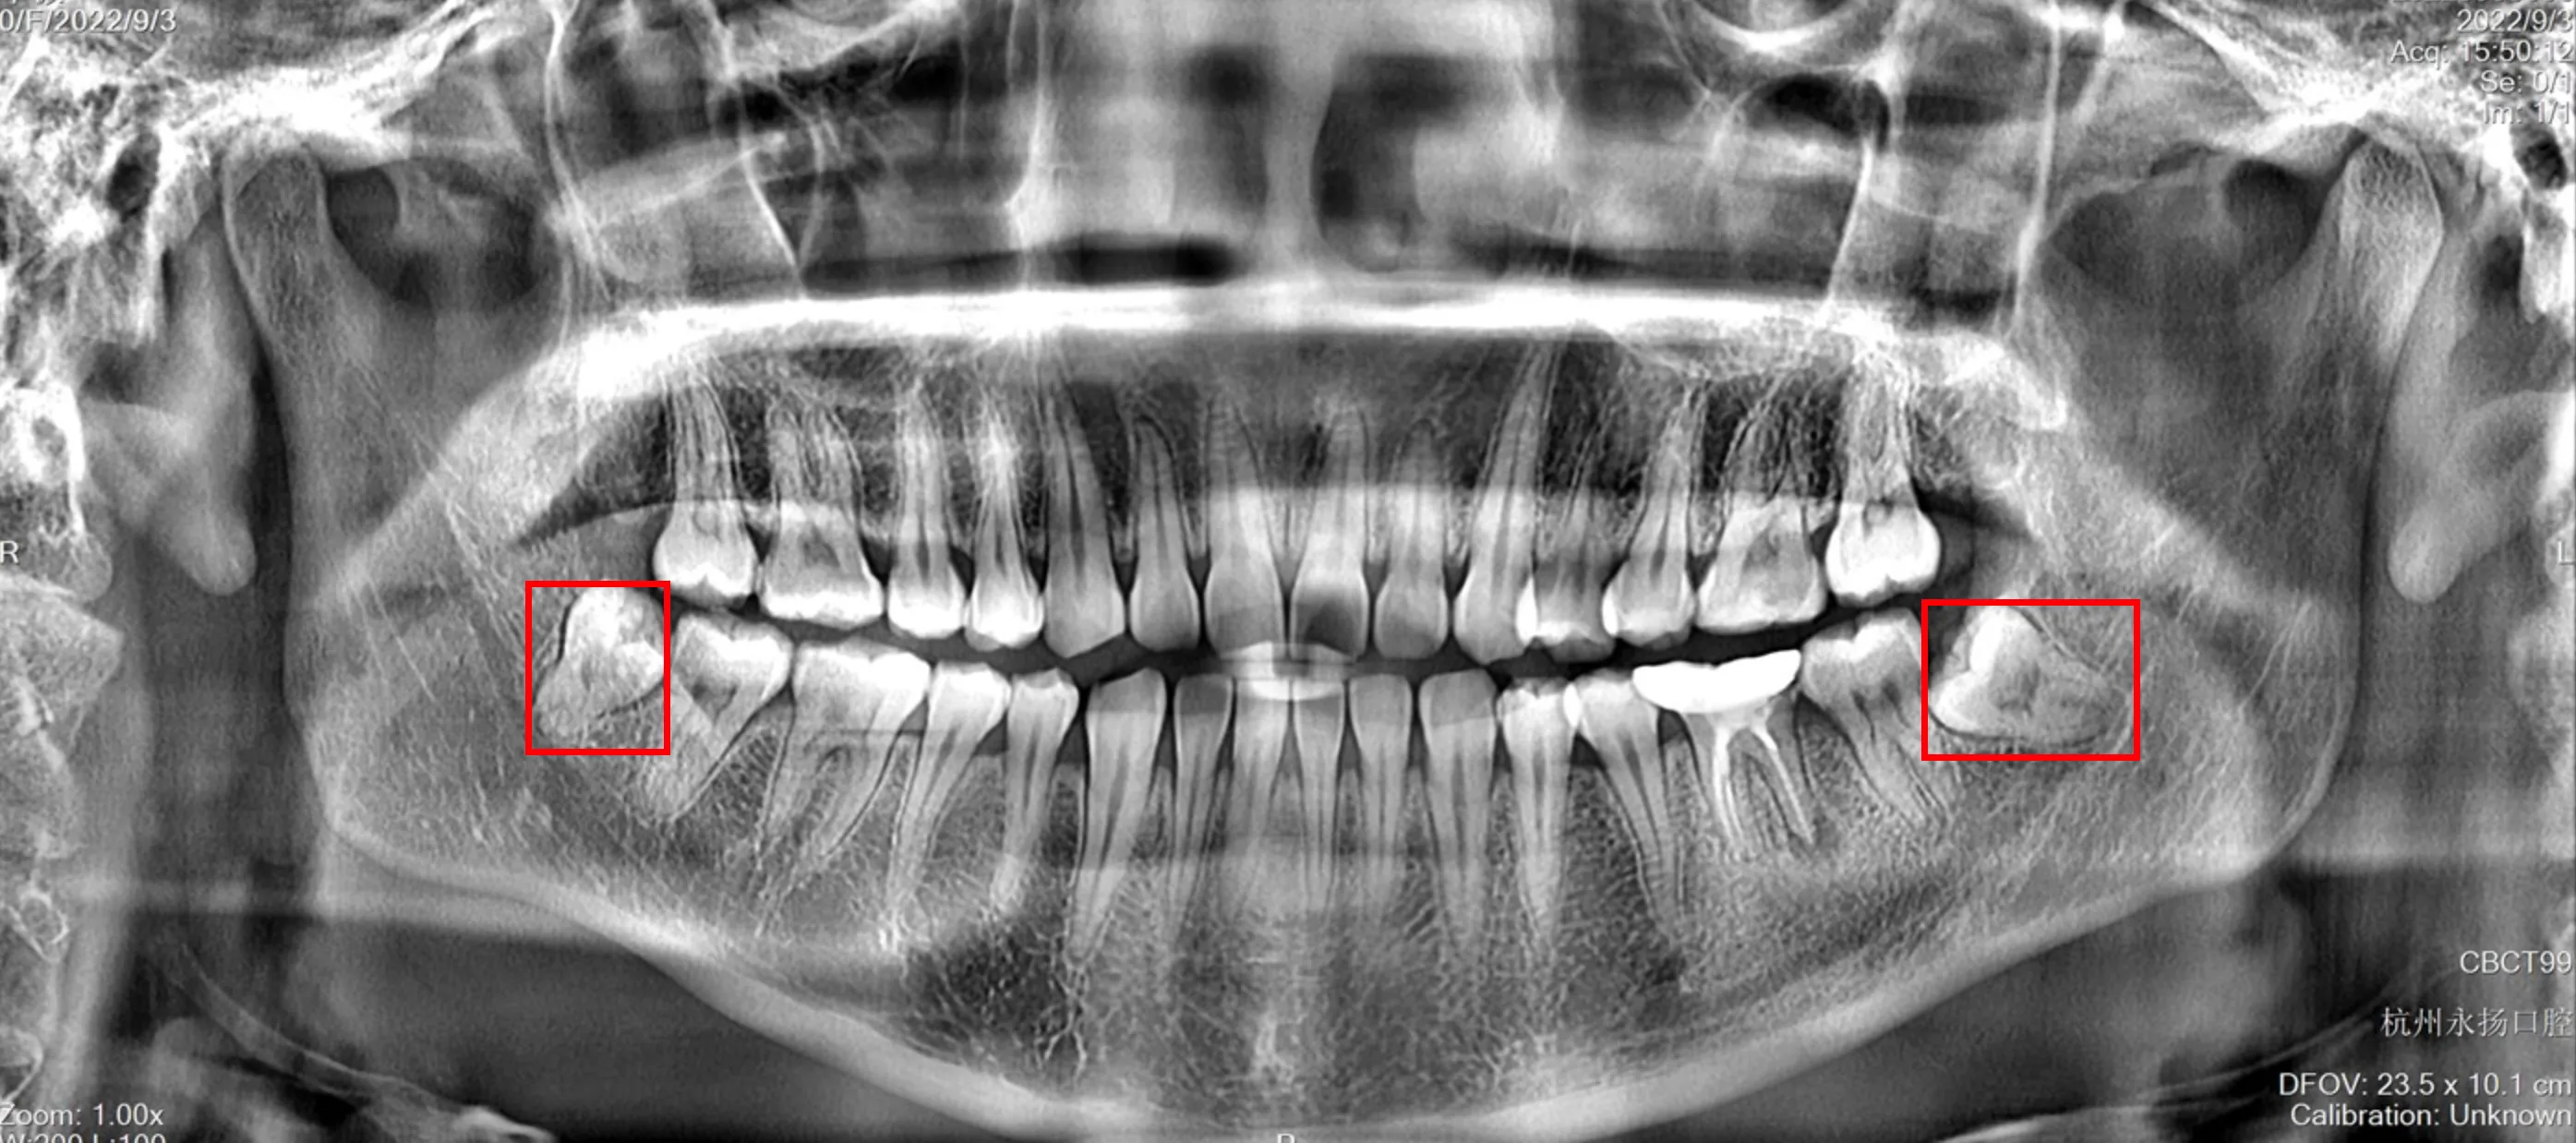

初步检查拍了个片子花费 58 ,医生看了片子表示难度较大,让我们去医院拔。

下面是图片,需要拔的是左边那颗,右边不疼,我女朋友还不想拔。